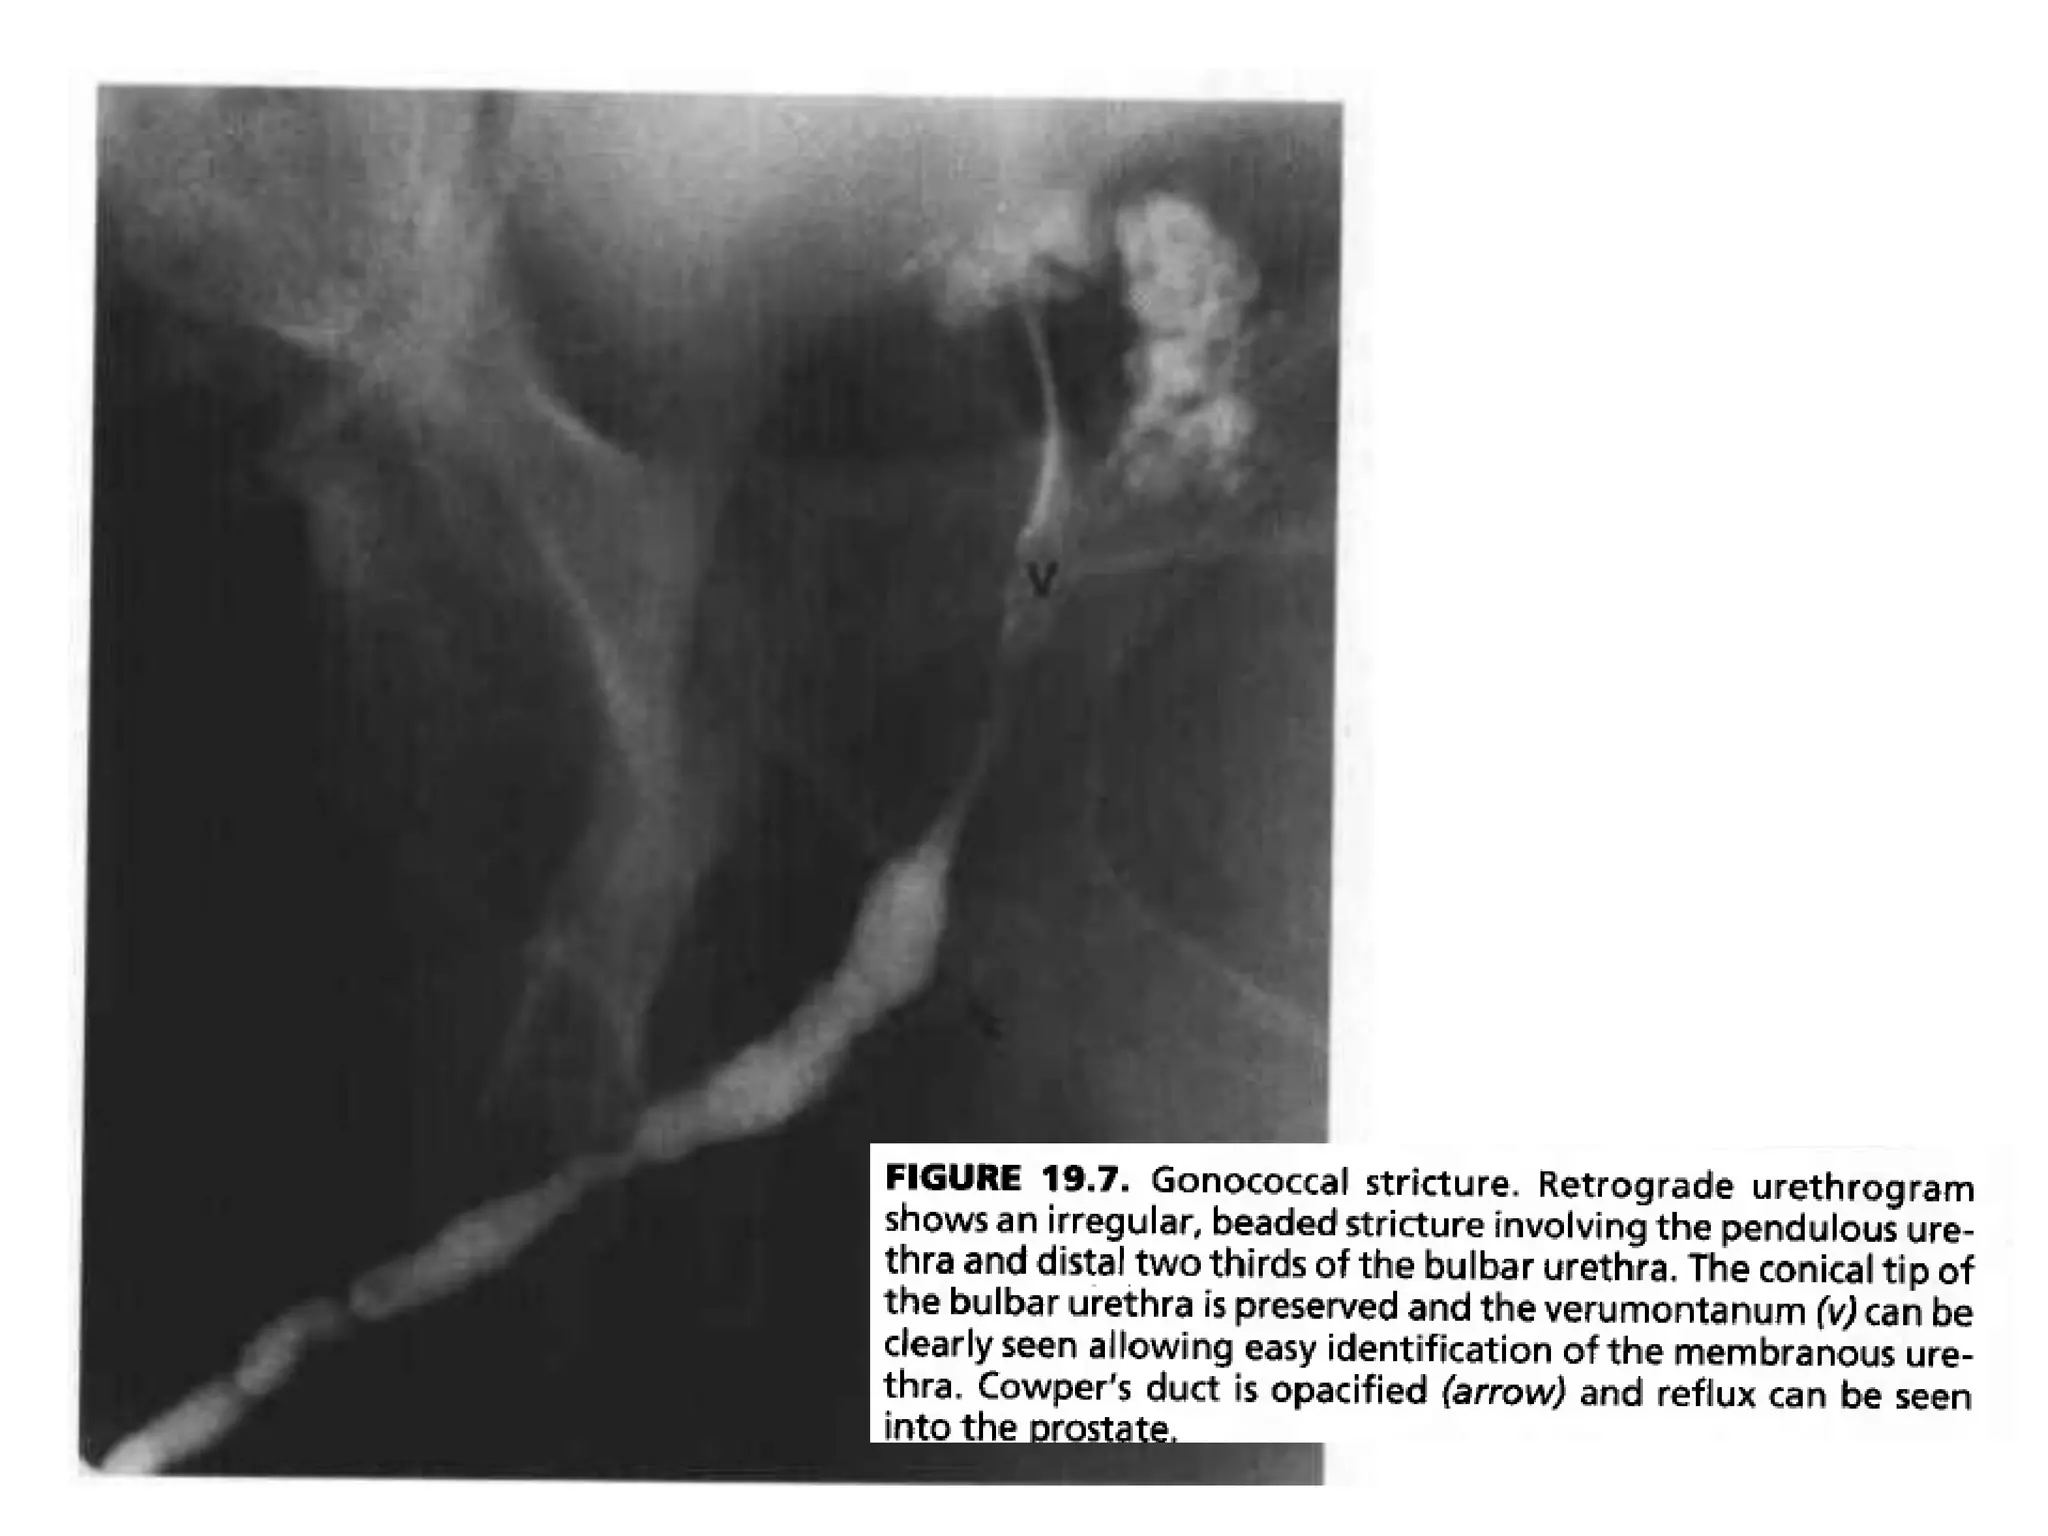

• The typical urethrographic finding in gonococcal urethral stricture is

an irregular urethral narrowing several centimeters long.

• While the bulbar urethra is the most common area of occurrence,

gonorrheal strictures may occur anywhere in the anterior urethra or

Gonococcal urethral stricture. Retrograde

urethrogram reveals a segment of irregular, beaded narrowing

in the distal bulbous urethra with opacification

of the left Cowper duct